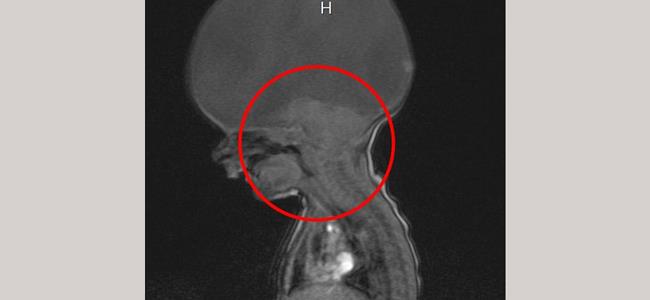

احتفل الطفل "آرون" الذي ولد بدون دماغ ، باستثناء قسم صغير في نهاية عنقه ، وهو الجزء الذي يسمح له بالتنفس والحركة فقط ،بعامه الثاني ، الأمر الذي شكل صدمة لوالدته التي علمت بالأمر بعد ولادتها بدقيقتين فيما أخبرها الأطباء أنه قد يموت في أي لحظة.

وشخص الأطباء مرض "آرون" بأنه اضطراب نادر يدعى "اندماج مقدم الدماغ"، إذ ولد مع جذع الدماغ فقط، وهو ما يسمح له بالحركة والتنفس، ولكن ليس لديه دماغ كامل .